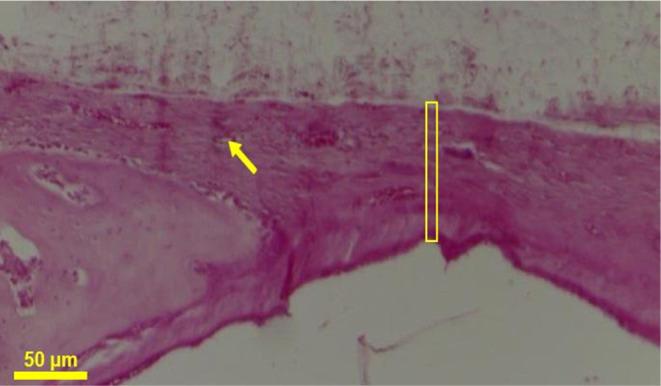

Functionalized scaffolds based on biodegradable polymers are materials used in bone tissue engineering. This study presents the development of functionalized fibrous scaffolds, fabricated from poly(ε-caprolactone) (PCL) and hydroxyapatite (HA). To produce this material, a short-distance electrospinning (ES) system was developed by adapting a 3D printer. The morphology and chemical properties of the scaffolds were evaluated using scanning electron microscopy, X-ray diffraction, Fourier-transform infrared spectroscopy, and thermogravimetric analysis. The results confirmed the porous structure and the presence of hydroxyapatite throughout the entire scaffold area. Mechanical tests indicated good elasticity and tensile strength of the scaffolds, favorable for bone regeneration. In vitro tests showed high levels of cell viability. Furthermore, in vivo experiments using a calvarial defect model in rats demonstrated that the PCL/HA scaffold promoted enhanced bone regeneration. Therefore, the PCL/HA scaffold developed through the adapted electrospinning system shows promise for bone repair.

基于可生物降解聚合物的功能化支架是骨组织工程中使用的材料。本研究展示了由聚(ε-己内酯)(PCL)和羟基磷灰石(HA)制成的功能化纤维支架的开发。为了生产这种材料,通过改装3D打印机开发了一种短距离静电纺丝(ES)系统。使用扫描电子显微镜、X射线衍射、傅里叶变换红外光谱和热重分析对支架的形态和化学性质进行了评估。结果证实了整个支架区域的多孔结构和羟基磷灰石的存在。力学测试表明支架具有良好的弹性和拉伸强度,有利于骨再生。体外测试显示细胞活力水平很高。此外,在大鼠颅骨缺损模型上进行的体内实验表明,PCL/HA支架促进了增强的骨再生。因此,通过改装的静电纺丝系统开发的PCL/HA支架在骨修复方面显示出前景。